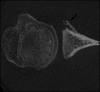

Glenoid articular cartilage lesion is a rare complication following traumatic anterior dislocation of the shoulder. We report the case of a 14-year-old male rugby player with traumatic anterior shoulder instability, an extensively flapped lesion on the glenoid articular cartilage, and an osseous Bankart lesion. Arthroscopic findings revealed that the glenoid cartilage was flap-detached, extending from the anteroinferior to the center. Repair of the osseous Bankart lesion using suture anchors and resection of the unstable peripheral part of the cartilage was performed arthroscopically. The main region of the injured articular surface was left untouched. During postoperative follow-up, absorption of the glenoid articular surface near the suture anchor holes was identified. Arthroscopic examination three months post-surgery showed that the flap detached lesion of the residual cartilage was stable and appeared adapted on the glenoid surface. The resected area was covered by fibrous tissue. A follow-up computed tomography scan revealed that the osseous lesion was united. The patient returned to his previous sports capacity eight months following the operation. At the 2-year-follow-up, magnetic resonance imaging revealed that the glenoid surface was remodeled to a flattened round shape with no signs of osteoarthritis, exhibiting proper conformity of the joint surfaces to the humeral head. Arthroscopic Bankart repair using suture anchors may cause bone resorption at the glenoid surface, leading to remodeling of the glenoid surface from the damaged glenoid cartilage lesion in young patients.